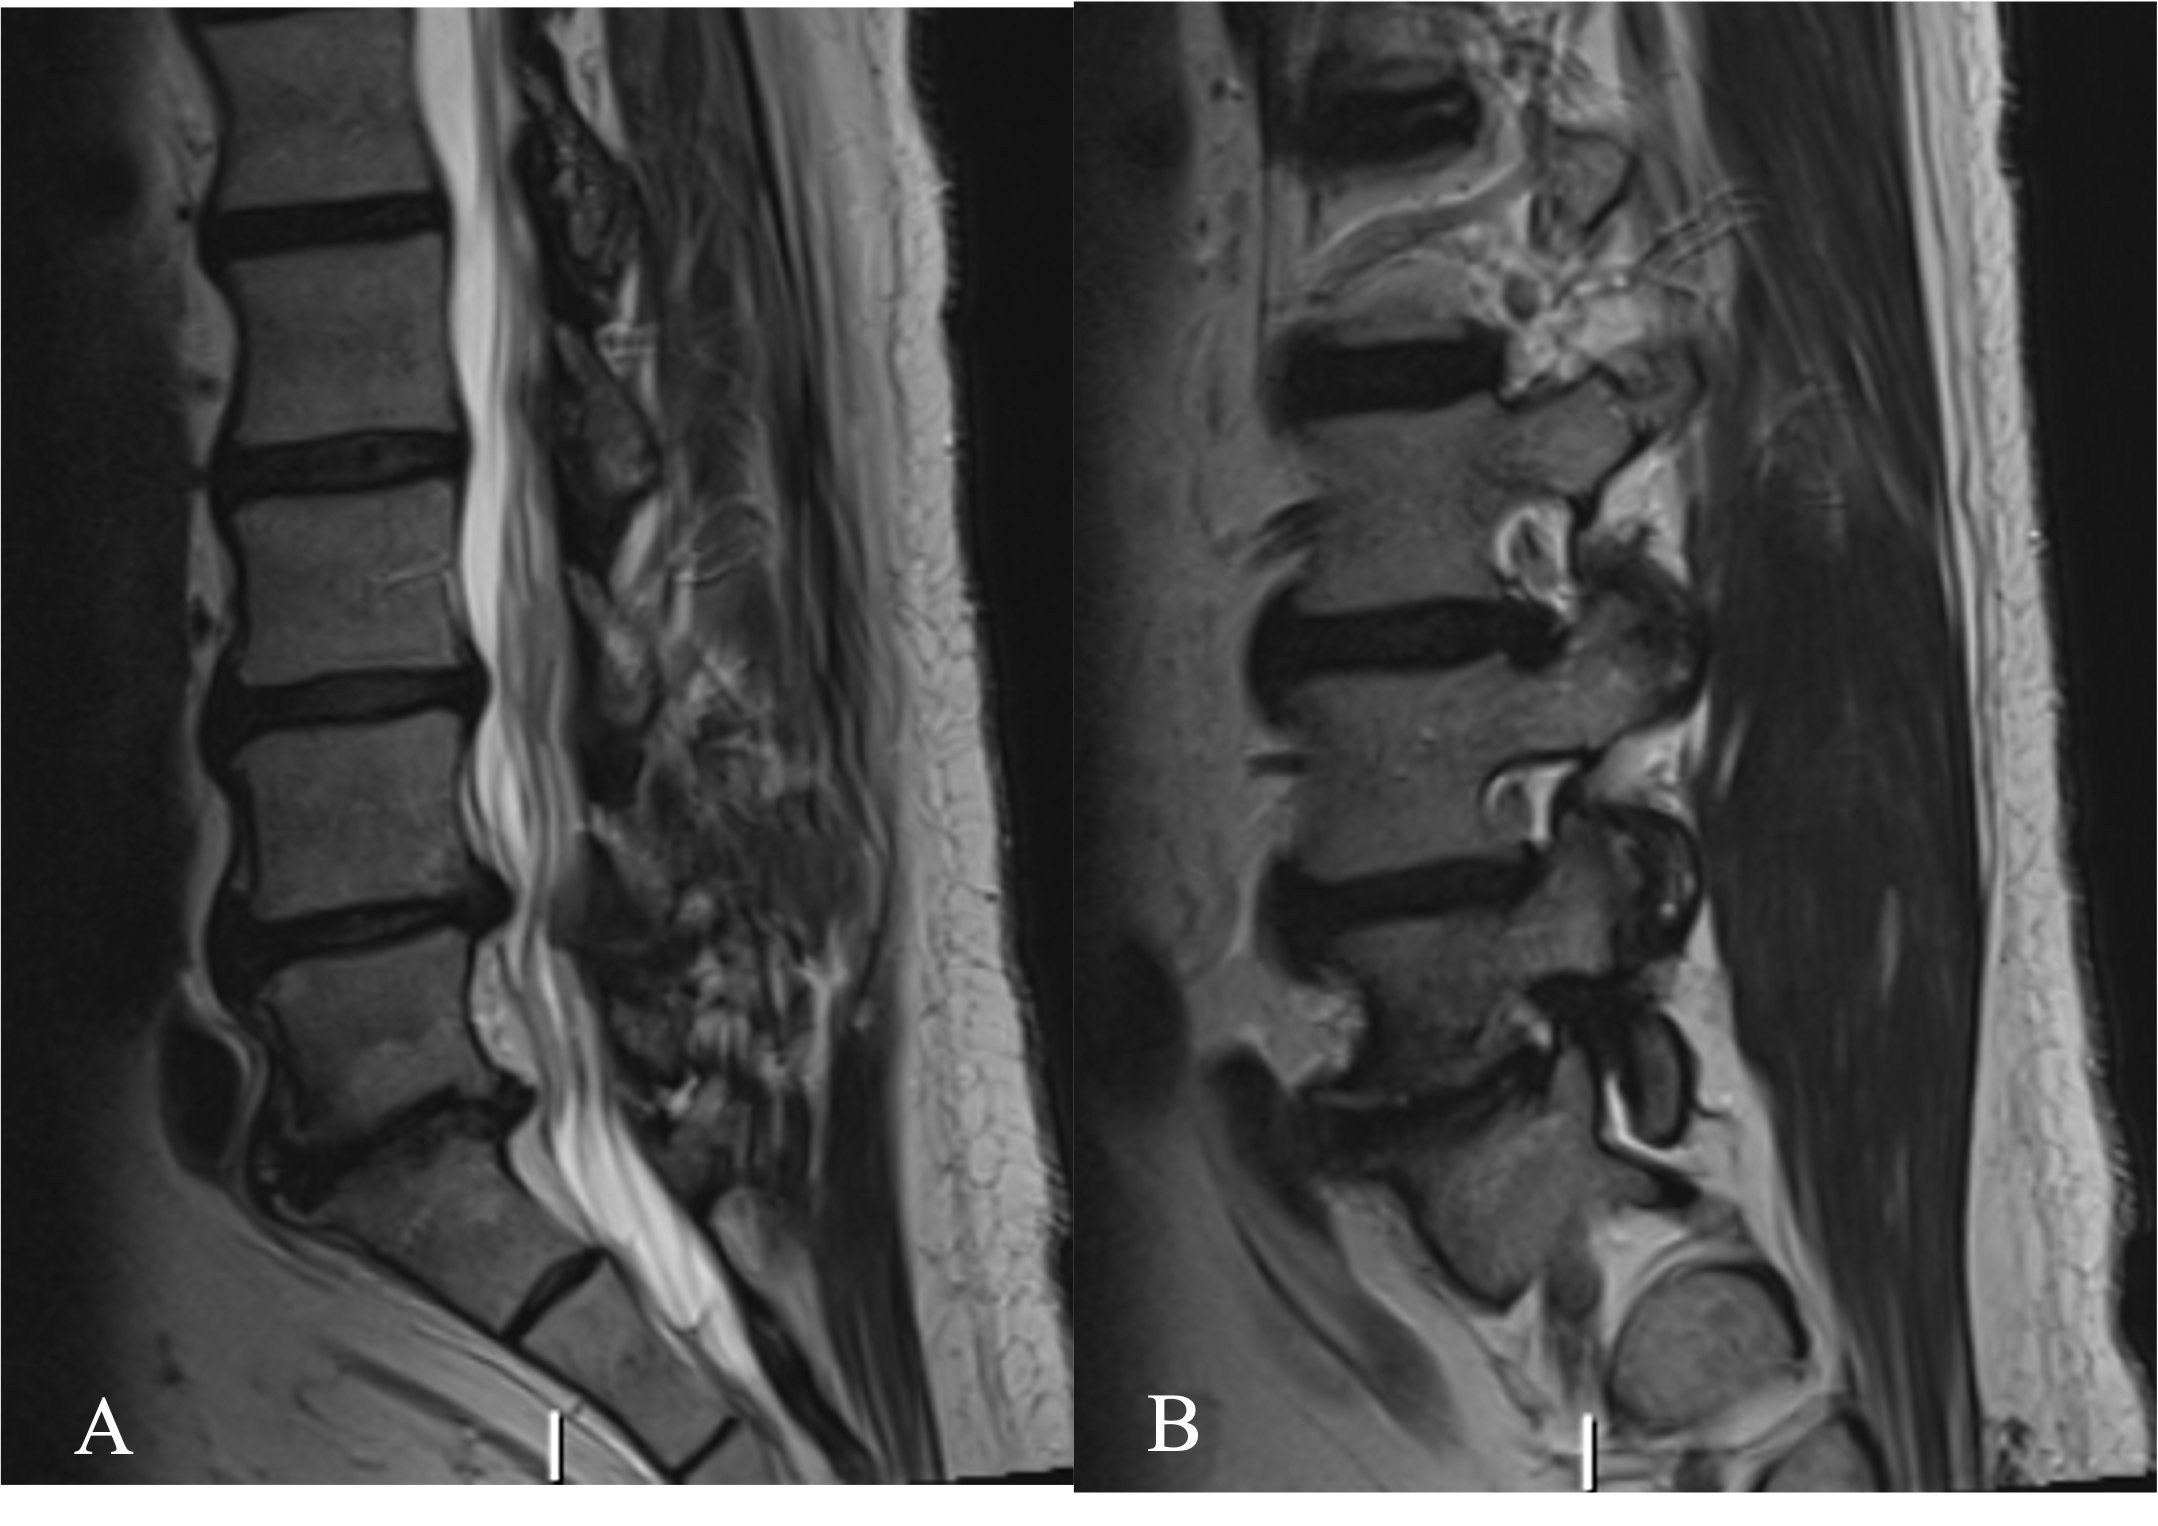

The patient was a 66-year-old male, presenting with axial low back pain and a painful left leg radiculopathy. He presented with an MRI that reveals advanced facet arthropathy at L4-5 and L5-S1 with degenerative disc disease (Figure 1). Furthermore, there was a severe degree of left sided L5-S1 neuroforaminal stenosis. Symptoms did not improve following 14 months of conservative management. Given the refractory nature of his symptoms to conservative measures, a minimally invasive TLIF at L4-5 and L5-S1 was recommended.